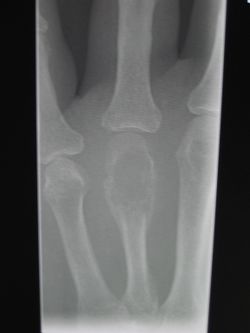

| Micrograph of an osteosarcoma, a malignant primary bone tumor. | |

- ساركومة عظمية Osteosarcoma، وهي أصابة تحدث أساسا ضمن انسجه العظام النامية.